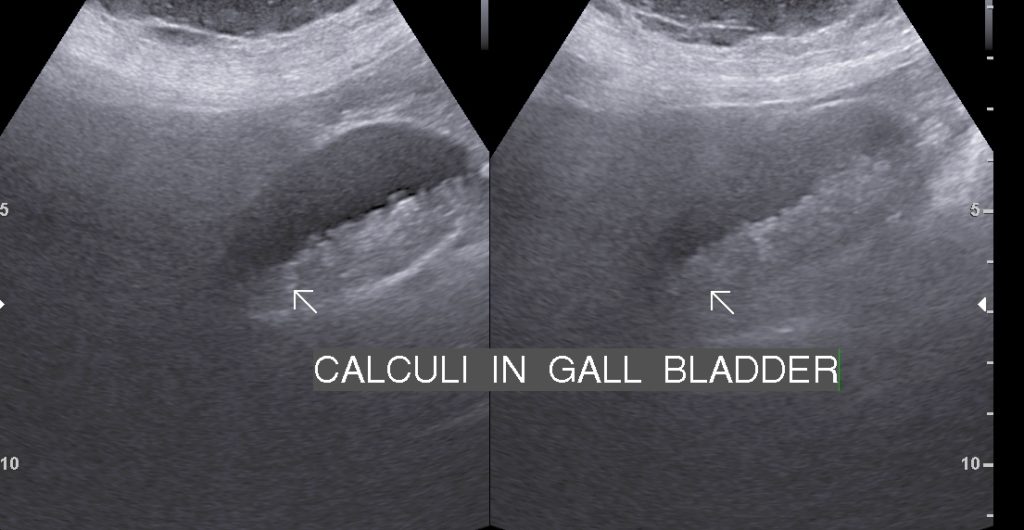

• Solitary Calculi: